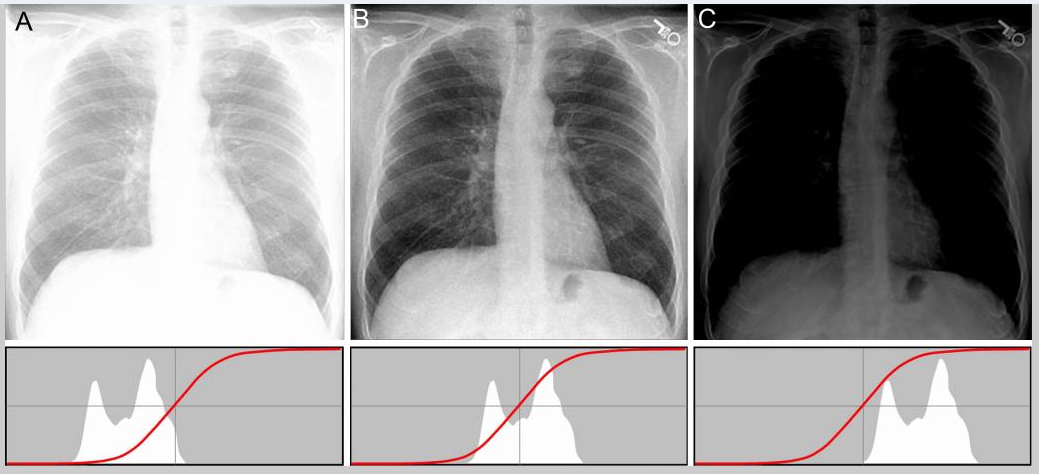

X-rays and their corresponding histograms. A is overexposed, B is just right, and C is underexposed. Notice how the histograms below the images shift with the exposure. Also notice that the exposure is the opposite from what we are used to seeing. Underexposed is "brighter" than overexposed. Adapted from The standardized exposure index for digital radiography.